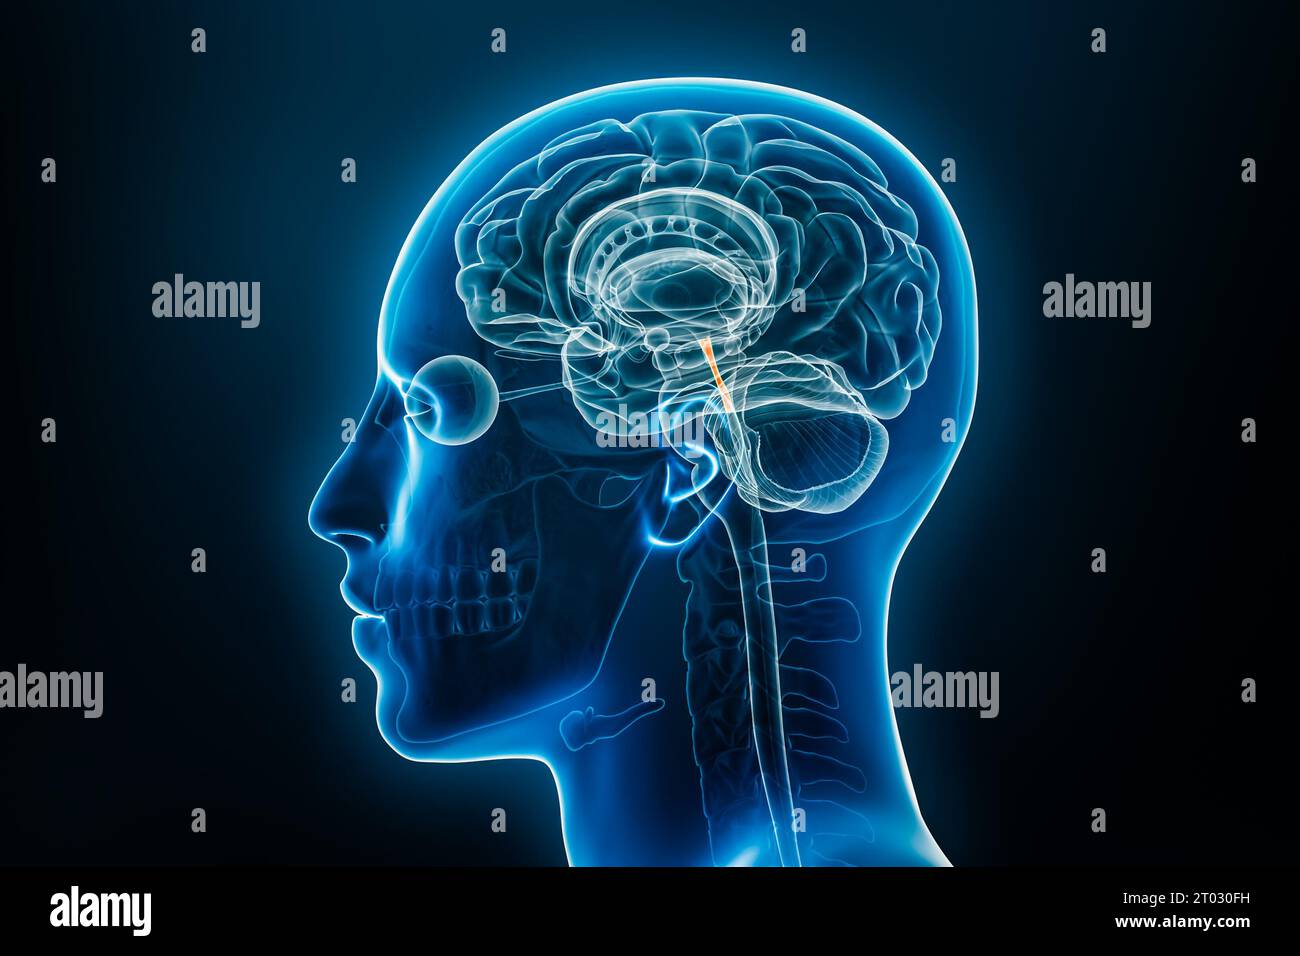

RF2T030FH–Röntgenprofilansicht des Sylvius oder des zentralen Aquädukts des Gehirns 3D-Rendering-Illustration. Menschliche Körperanatomie, Medizin, Biologie, Wissenschaft, Neurowissenschaft,